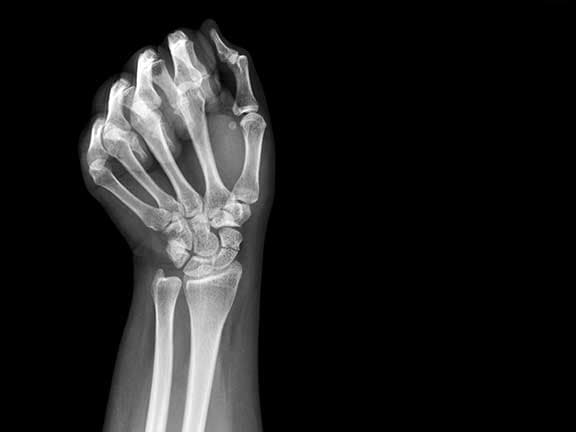

Skafoid kırığı teşhisinde öncelikle doktor fizik muayene yapmalıdır. Bu muayene esnasında el bileğinden başparmağa doğru bastırılması sonucunda ağrı oluşabilir. Muayene sırasında ayrıca, hastanın el bileğinde hareket kısıtlılığı olup olmadığı ve günlük aktivitelerini nasıl etkilediği de değerlendirilir. Şüpheli hastalarda özellikle radyolojik inceleme sırasında skafoid kemiğe dikkat etmek gerekir. Çünkü özellikle kırığın oluştuğu ilk gün skafoid kırığı belli olmayabilir. Bu gibi durumlarda hastanın el bileği atele alınmalıdır. Bunun ardından 10 gün sonra yeniden film çekilmesi gerekir. Ancak mümkünse 10 gün beklemek yerine, MR ya da bilgisayarlı tomografi yöntemleri ile bir an önce kırık tespit edilmeli ve tedaviye başlanmalıdır. Ayrıca, bazı durumlarda ultrason incelemesi de faydalı olabilir, çünkü bu yöntemle yumuşak doku yaralanmaları daha iyi değerlendirilir.

Skafoid Kırığı teşhisinde öncelikle doktor fizik muayene yapmalıdır. Bu muayene esnasında el bileğinden başparmağa doğru bastırılması sonucunda ağrı oluşabilir. Şüpheli hastalarda özellikle radyolojik inceleme sırasında skafoid kemiğe dikkat etmek gerekir. Çünkü özellikle kırığın oluştuğu ilk gün skafoid kırığı belli olmayabilir. Bu gibi durumlarda hastanın el bileği atele alınmalıdır. Bunun ardından 10 gün sonra yeniden film çekilmesi gerekir. Ancak mümkünse 10 gün beklemek yerine, MR ya da bilgisayarlı tomogrofi yöntemleri ile bir an önce kırık tespit edilmeli ve tedaviye başlanmalıdır.